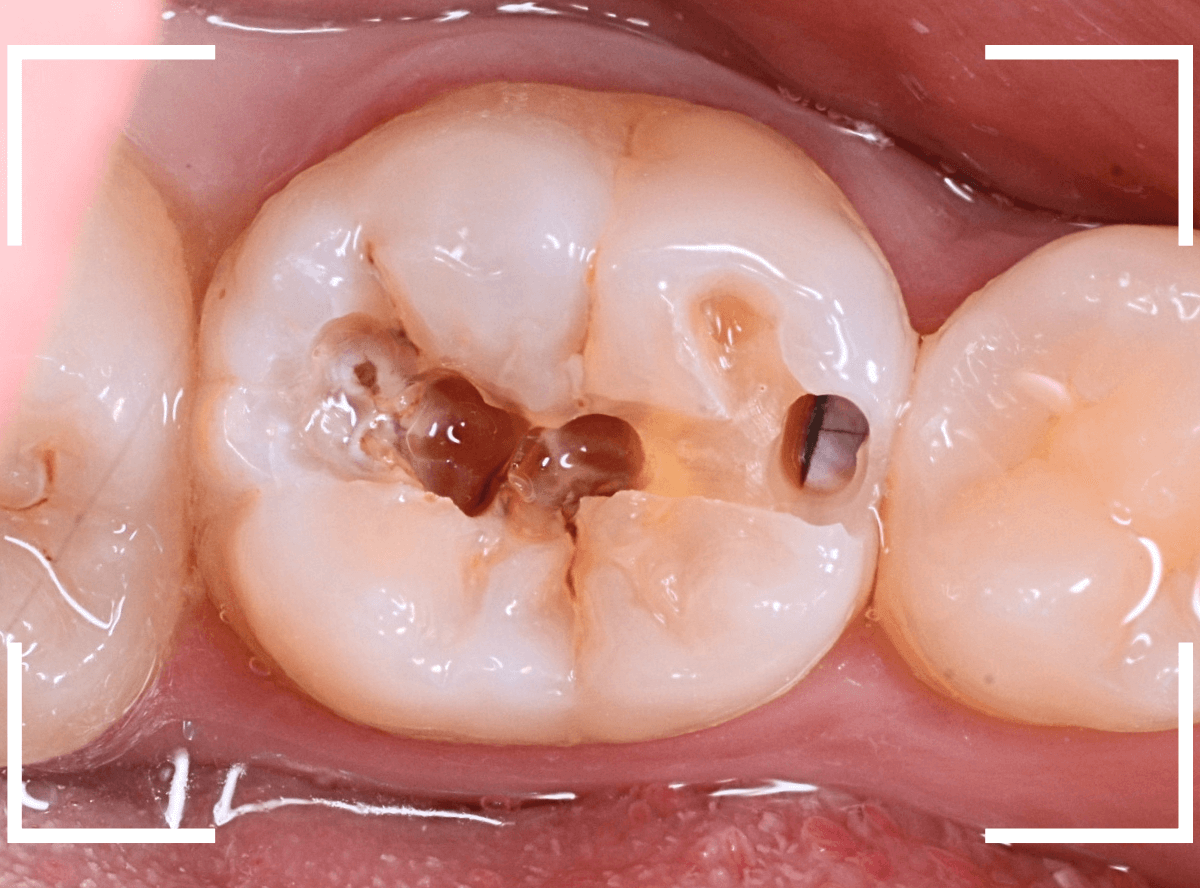

Case.5 症状もなく、神経の近くまで深く広がっている小窩裂溝う蝕

今回は、症状もなく、見た目には小さく見える、小窩裂溝う蝕の例です。

レントゲン写真で確認すると、今回はとても大きな虫歯になっている事が確認出来ました。

かなり神経の近くまで虫歯が進行しているのがわかります。

裂溝部分を少し削ると、中は虫歯で大きな空洞になっていました。

ある程度、虫歯を除去したところで、う蝕検知液で確認します。

真っ赤に染まり、まだ虫歯が取り切れていないのがわかります。

神経まで近づいてきたので、慎重に虫歯を除去します。

全ての虫歯を除去したところです。

神経スレスレのところまで虫歯が広がっていました。